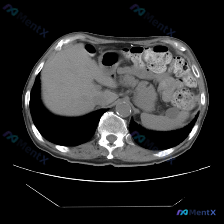

这是一张腹部CT横断面软组织窗图像:

- 脾脏:形态可见,密度均匀,没有看到明确的增大,也没有局灶性的高低密度病变;

- 其他实质脏器:肝脏、胰腺体尾部的形态和密度也都没看到显著异常;

- 血管与腹膜后:腹主动脉壁有斑点状钙化(这是个常见的老年性改变),但周围没有明确的肿大淋巴结;

- 其他:没有腹水,没有明显的肠梗阻或肠壁增厚。

一句话总结:这张图像层面里,脾脏是正常的,没有发现任何特异性异常。